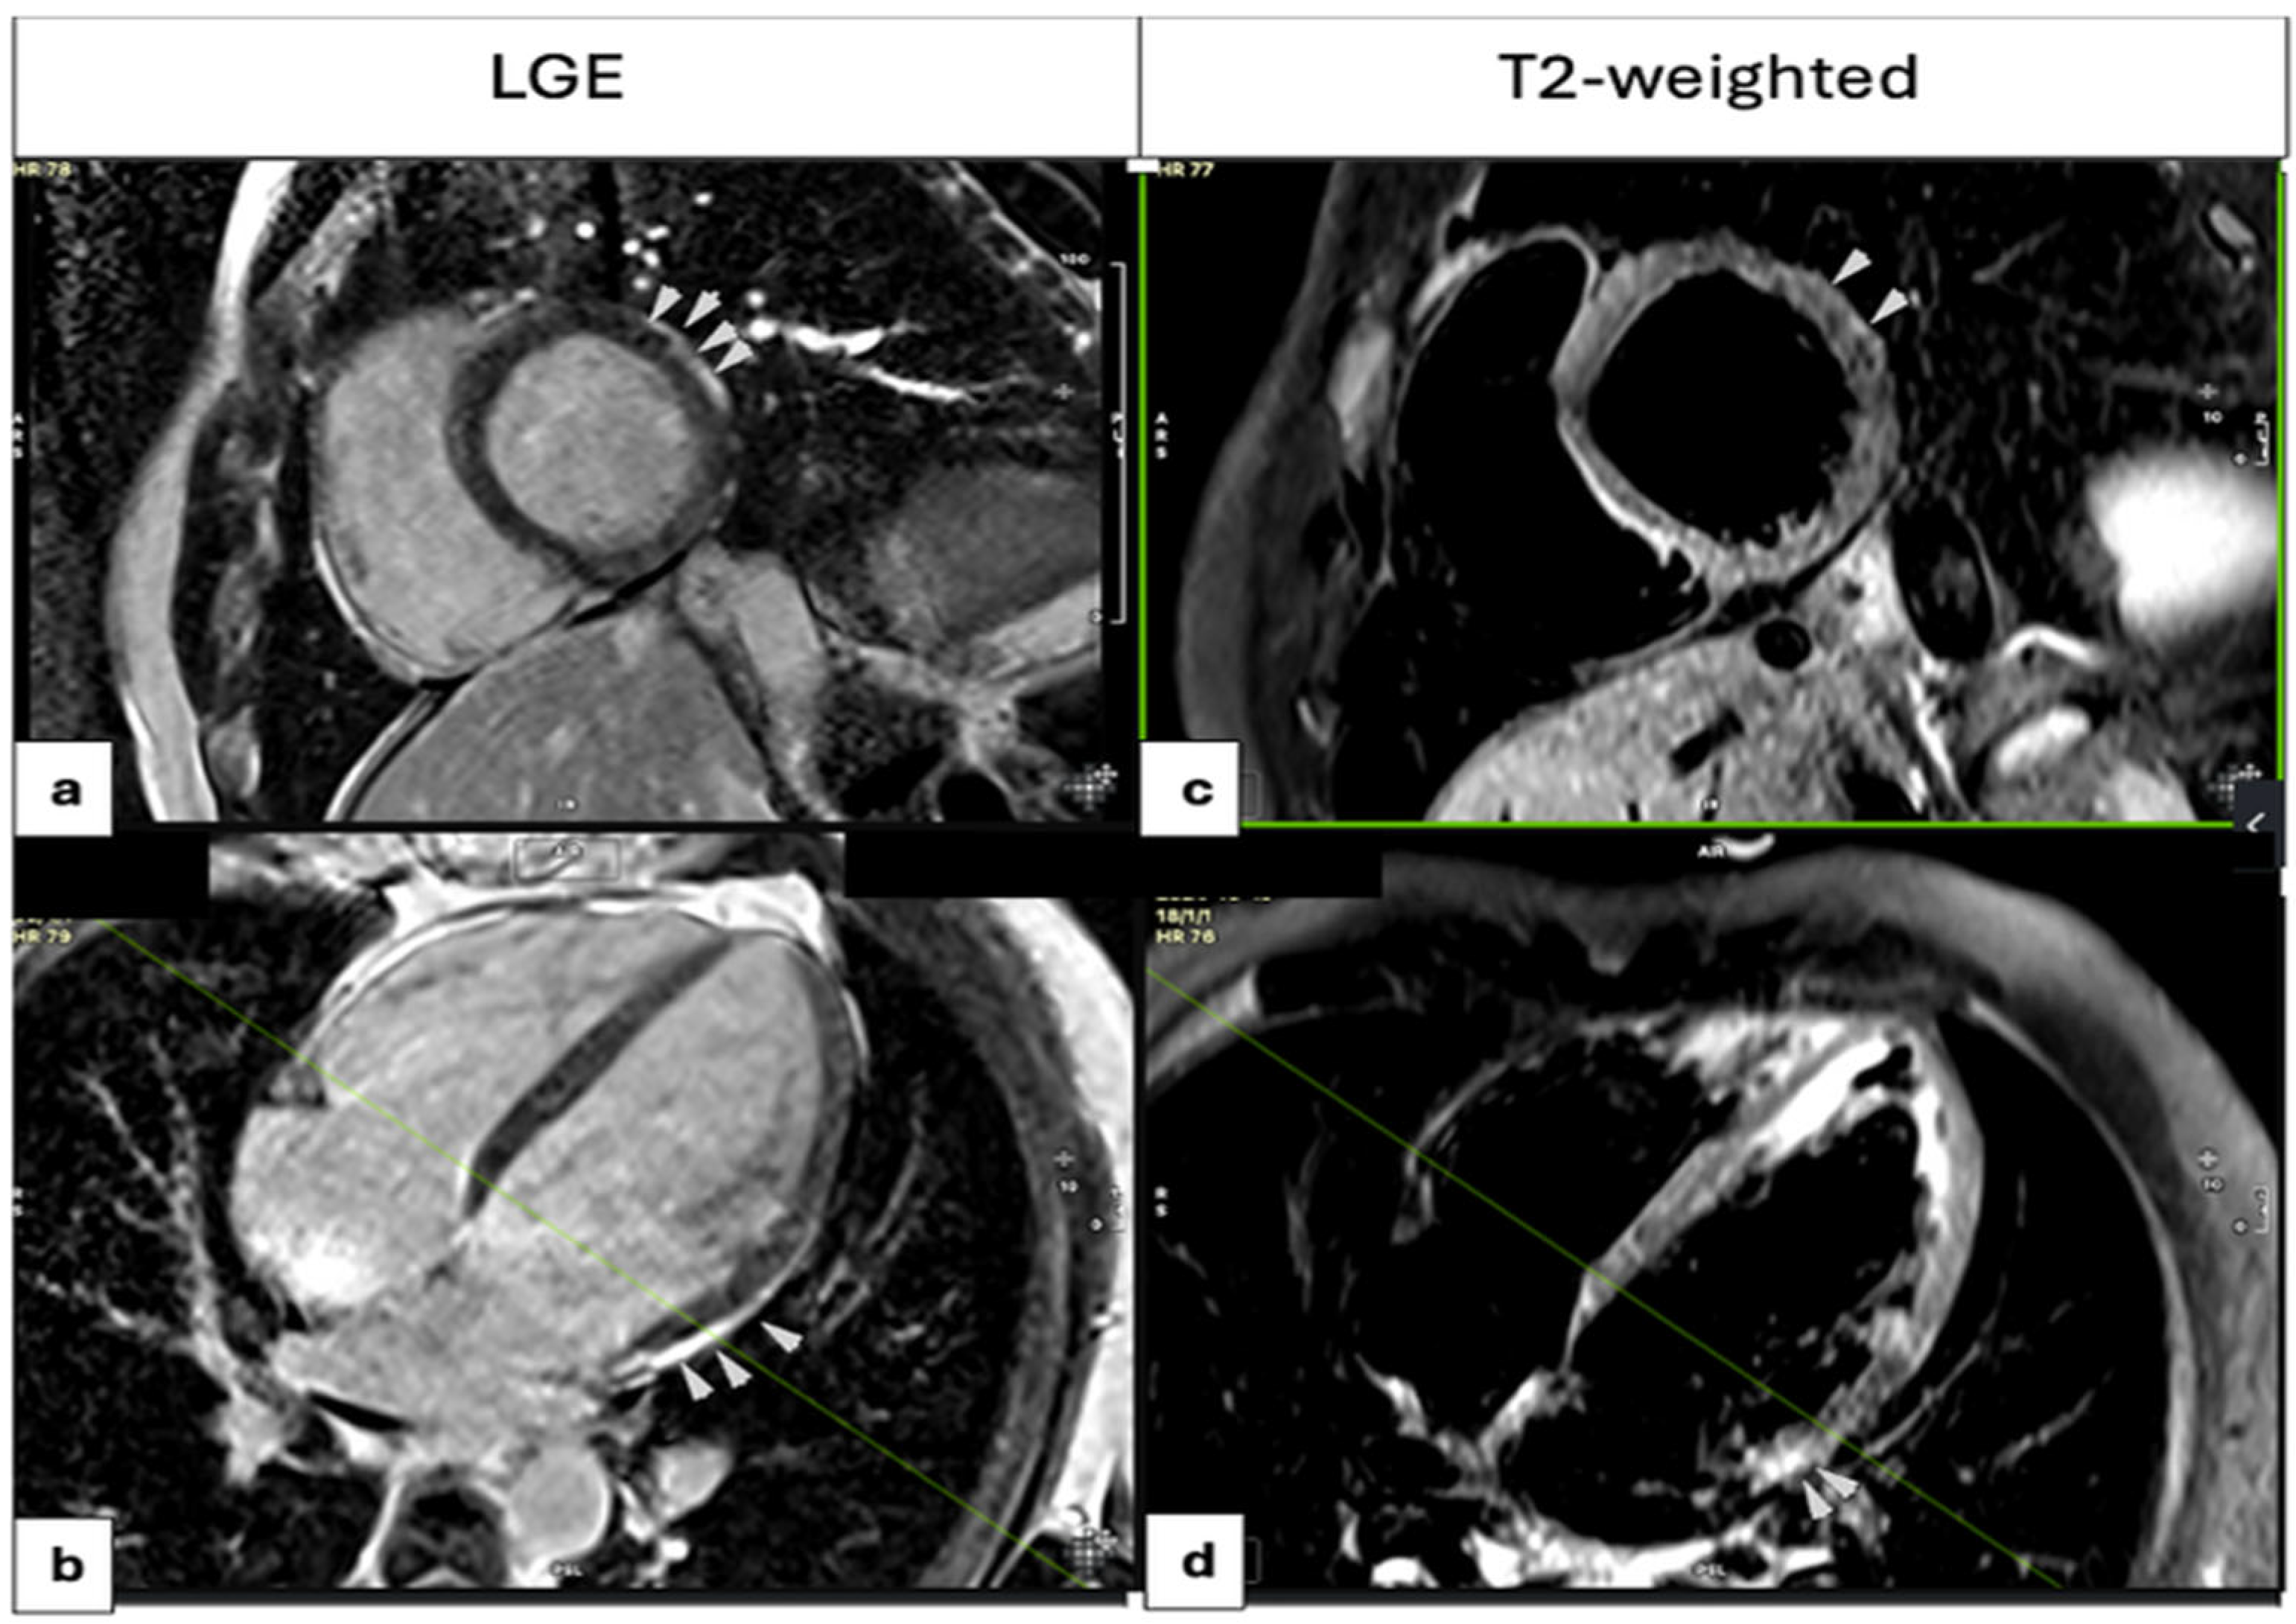

Following admission, CMR imaging was performed within a median period of 8 days (IQR: 5–16 days). CMR-based RWMAs were identified in less patients (13.0%) than in TTE, while a diffuse mild hypokinesia was mostly reported with a low impact on the absolute values of the LVEF, presumably due to the young age of participants. The observed discrepancy between TTE and CMR findings may also be attributed to the difference in timing between the two examinations, with TTE typically performed on the first day of hospitalization and CMR on or around the eighth day. Given the dynamic nature of acute myocarditis, evolving myocardial function over time could explain this variation. Fibrosis was defined by the presence of LGE on CMR, which was detected in 69 patients (80.2%), primarily localized to the subepicardial region of the basal and mid segments of the inferolateral and lateral walls (Supplementary Figure S1). The midwall distribution and transmural involvement of LGE were uncommon (7.0% and 5.8% of cases, respectively). Myocardial edema was assessed using T2-weighted (T2W) imaging and was present in 65 patients (75.6%). Early gadolinium enhancement and mild pericardial effusion were infrequently observed (9.9% and 22.2% of patients). Other rare findings were the right ventricular thrombus (1 patient), pleural effusion, and underlying lung abnormalities (1 patient). Figure 3 illustrates the distribution of LGE and corresponding T2-weighted imaging findings. Of the patients, 34 underwent invasive coronary angiography, while the rest received coronary computed angiography to rule out CAD.

Figure 3.

LGE distribution (a,b) and T2-weighted images (c,d). High-intensity signal (white arrows in the basal anterolateral wall segment on T2-weighted images (c,d)) indicates myocardial edema, with corresponding LGE in the same regions (a,b), findings consistent with acute myocarditis.